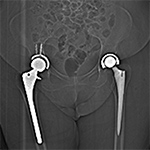

Artifact Summation. (A) Scout image demonstrates bilateral total hip arthroplasties. (B) Axial CT image at the level of acetabular cup and femoral head shows severe transverse streaking related to total summed attenuation of metal components. Optimal Windowing. (A) Axial CT image of the pelvis viewed in soft tissue windows demonstrates extensive streak artifact due to total hip arthroplasty prohibiting evaluation of adjacent bone and soft tissue structure. (B) Same axial CT image set to bone windows results in improved visibility of adjacent bone and soft tissue anatomy.